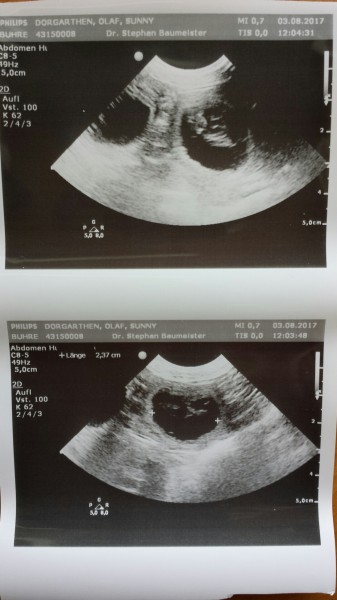

Auf dem unteren Foto sieht man die Abmessung der Fruchtblase...2,37cm. Die Föten haben eine Grösse, fast wie ein Gummibärchen ;-)